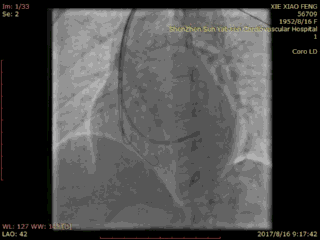

术前冠脉造影

血管选择 一

血管选择二

血管选择三